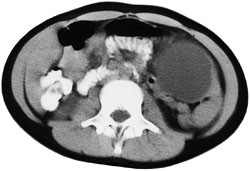

Pasient 2. 14 år gammel gutt, tidligere frisk. To måneder før diagnosen av miltcyste ble erkjent, fikk han et stumpt slag mot venstre nedre forside av brystet. Han hadde smerter i noen dager, men glemte så det hele. Seks uker senere kjente han hevelse under venstre ribbebue, og merket også litt ubehag ved fysisk anstrengelse. CT viste en cyste medialt i milten, med nærmest normal milt lateralt (fig 2). Cysten målte 16 ⋅ 13 ⋅ 13 cm. Septa ble beskrevet, men bare et lokulament. Echinokokkserologisk undersøkelse var negativ. Pasienten ble operert i 30˚ høyre sideleie. Cysten ble punktert og tømt for strågul væske. Den ble mobilisert fra venstre hemidiafragma og fra undersiden av venstre leverlapp, der den satt fast med brede adheranser. Cysten ble resecert ved deling av veggen ved overgangen til normalt miltvev. Veggtykkelsen var om lag  cm, og det var uttalt trabekulering av cystens indre vegg. Resektatet, som målte 16 ⋅ 11 cm, ble fjernet i pose via portåpningen i venstre fossa iliaca, som ble utvidet til 2 cm. Det var et ukomplisert per- og postoperativt forløp. Histologisk undersøkelse viste fibrøs miltcystevegg med stedvis plateepitelkledning (fig 3).